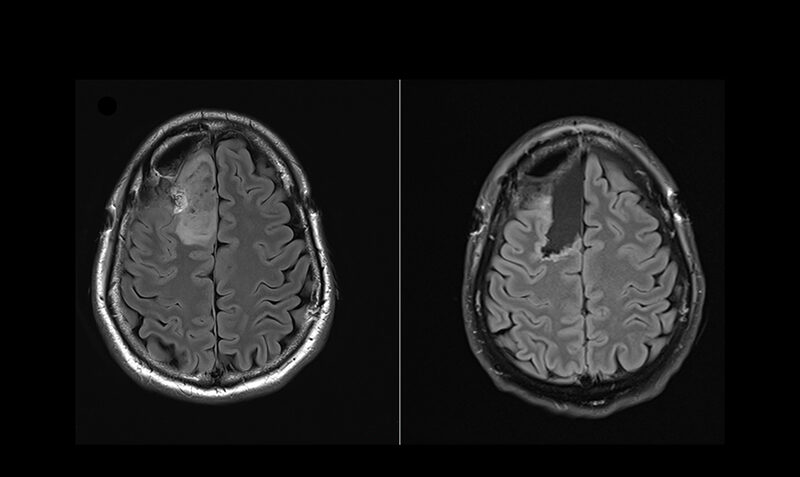

Brain scans from a patient in the world-first clinical trial, where researchers were able to compare tumour samples taken before treatment (left) and after treatment (right). The pioneering Brain Perioperative clinical trial platform aims to accelerate drug development and improve outcomes for brain cancer patients.

Analysis of brain tumour samples before (left) and after treatment (right) revealed increased immune activation (shown in green), following treatment with the IDH inhibitor.